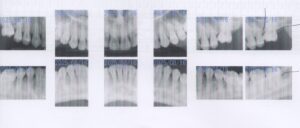

左上第一大臼歯がありません。そのせいか矯正中に第二大臼歯が近心に傾いています。

そのため第二大臼歯近心の下は歯磨きができません。そのため歯が染みています。

矯正中とのことなので第二大臼歯を遠心に移動し、第一大臼歯にインプラントを入れることを勧めました。

矯正中とのことなので第二大臼歯を遠心に移動し、第一大臼歯にインプラントを入れることを勧めました